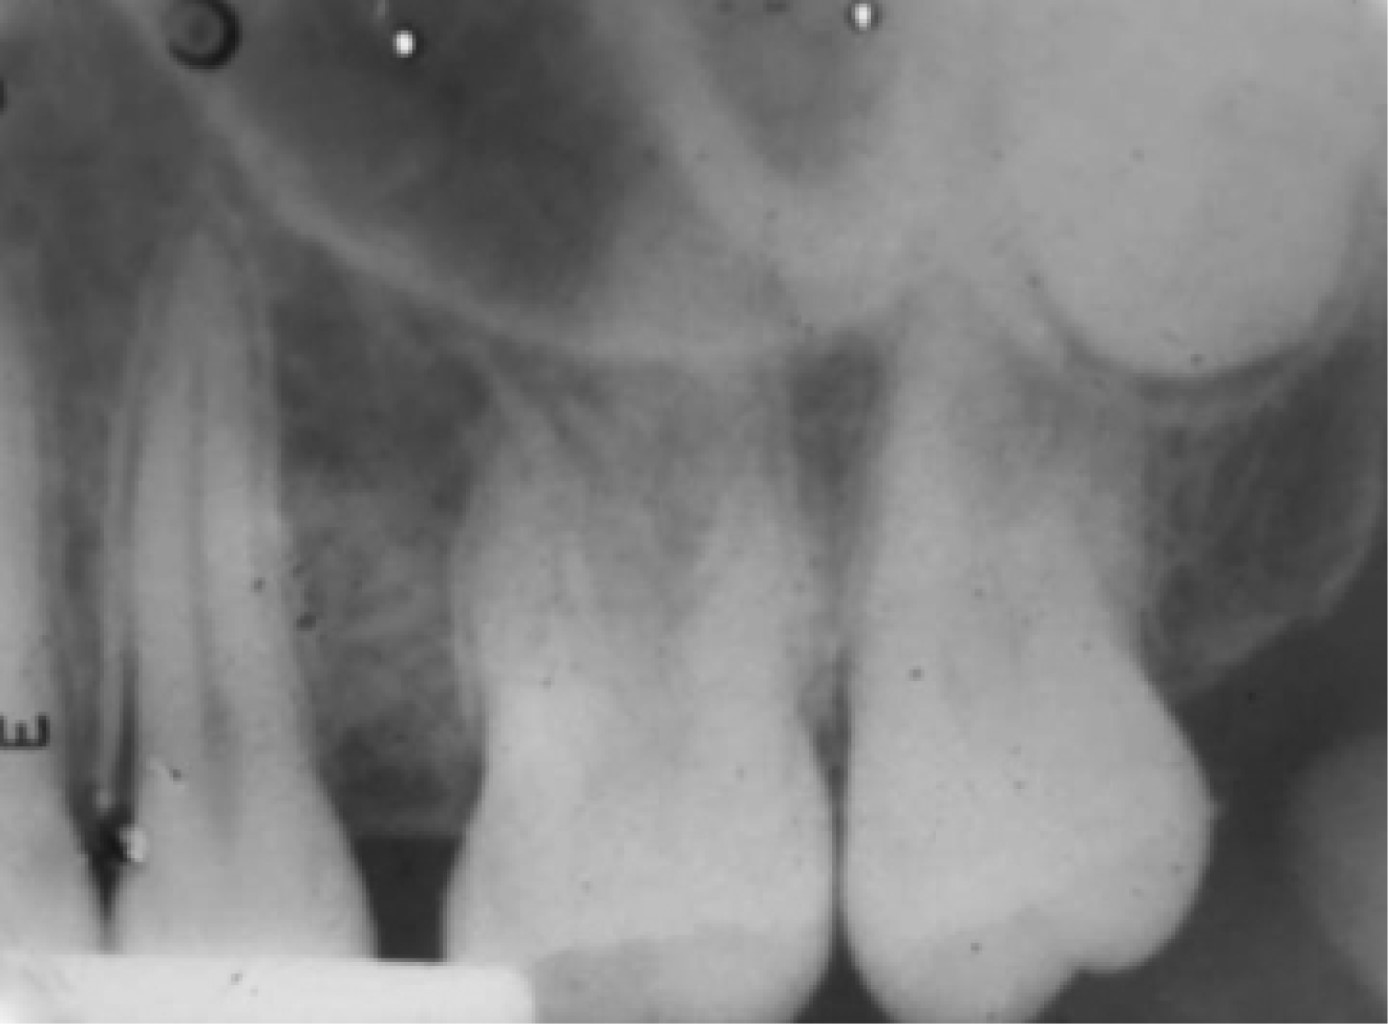

Figure 1